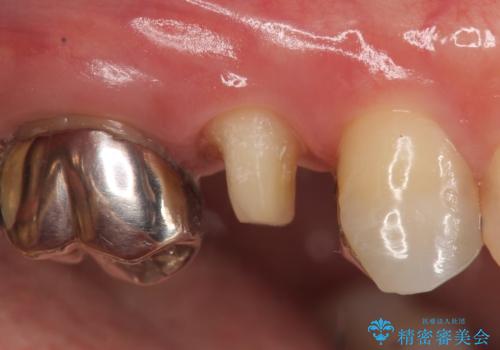

- 右上5番目の歯がなにもしなくてもズキズキ痛むので診て欲しいといらっしゃった方の症例です。

診査の結果神経を保存するのは困難だったため、根管治療を行った後、オールセラミッククラウンによる補綴を行いました。